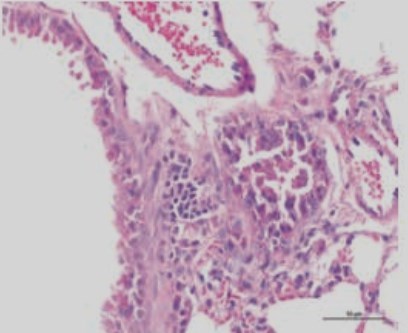

Lung microphotograph after 16 weeks of smoke

Cigarette smoking is known to induce serious lung diseases, but there is not an effective method to solve this problem. The present study investigated vitamin D3 on over-expression of CXCR3 and CXCL10 in mice induced by cigarette smoking. A pulmonary airway model was designed, and morphological assessment of emphysema, IL-4, IFN-γ and CXCL10 concentration in bronchoalveolar lavage fluids, expression of CXCR3 and CXCL10 were detected. Emphysema of the mice only exposed to cigarette smoke was significant, and concentration of IL-4, IFN-γ and CXCL10 was also increased. In addition, CXCR3 and CXCL10 were over-expressed. The degree of emphysema, concentration of IL-4, IFN-γ and CXCL10, and expression of CXCR3 and CXCL10 in mice administrated with low dose vitamin D3 were similar to the normally treated mice. Low dose of vitamin D3 can effectively protect the lung from the damage induced by cigarette smoke.